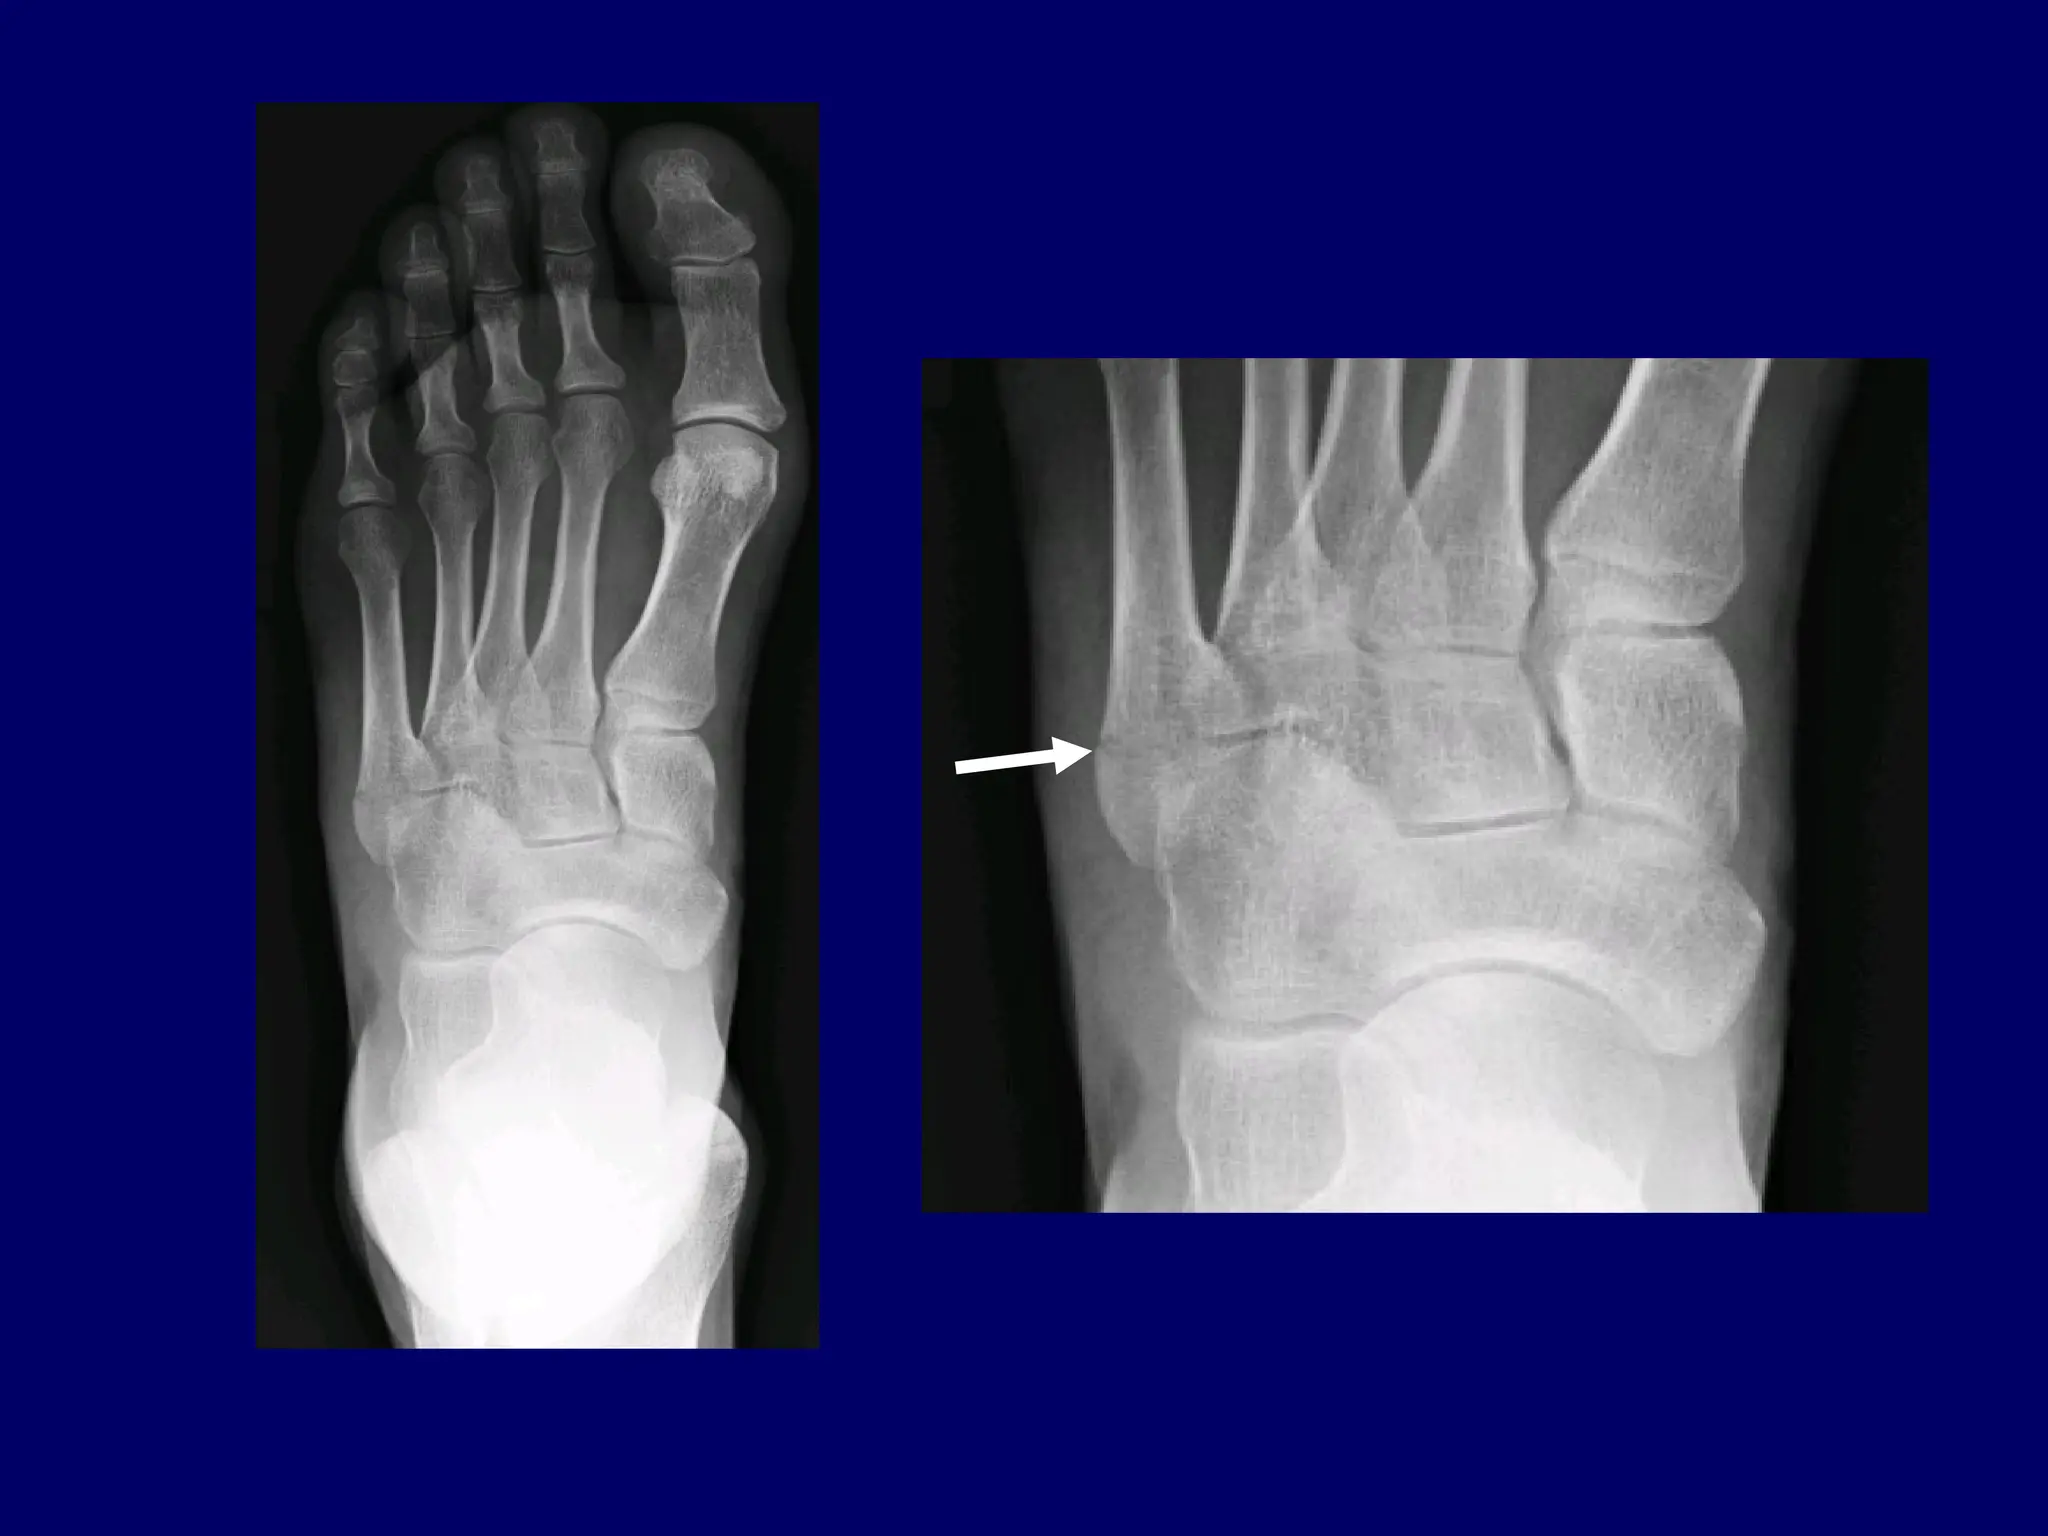

History: 11 y/o twisting

injury of the foot

History: 11 y/otwisting injury of the foot

1. 2. 3. 4. Please name thesebones Word bank: Cuboid Navicular Medial cuneiform Os naviculare